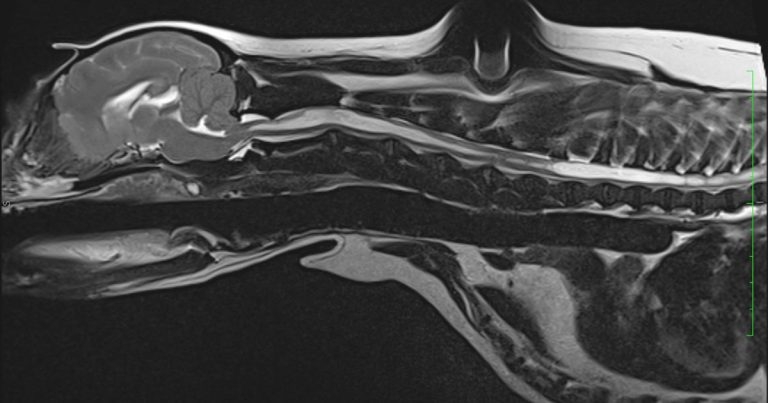

Figure 1. T2-weighted sagittal MRI scan of the six-year-old cavalier King Charles spaniel.

T2-weighted (T2W; Figure 1) and T1-weighted (T1W) sagittal scans showed a significant cavitation located within the spinal cord, extending from C1 to L4.

The T2W transverse scan through the cord showed cavitation of approximately 75% of the cord diameter and had an oval shape, asymmetrically affecting the dorsal horn of the grey matter.

The occipital bone was displaced rostrally, causing a caudoventral portion of the cerebellar vermis to herniate through the foramen magnum, displacement of the caudoventral segment of the cerebellum, and decreased volume of the caudal cranial fossa.

Transverse T2W images through the brain revealed mild-to-moderate dilation of the third ventricle and obstruction of the CSF.

The findings were compatible with that of a profuse Chiari-like malformation (CM), and severe cervical and thoracolumbar syringomyelia.